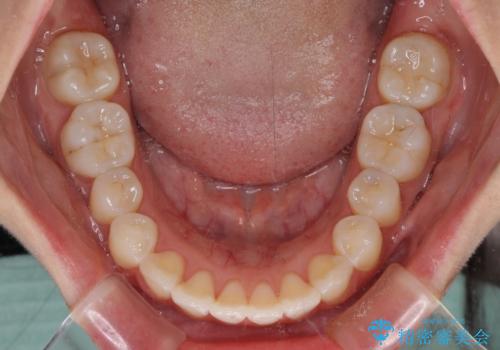

- 上下前歯のデコボコを気にして来院された患者様です。

インビザラインによる上下歯列の拡大と、IPR(歯と歯の間を削る)にるスペースの獲得により、前歯のデコボコを改善することとしました。

しっかりと装着時間を遵守してくださったので、思い通りの歯列に整えることができました。

結婚式前に終了させることができ、患者様には大変満足していただきました。